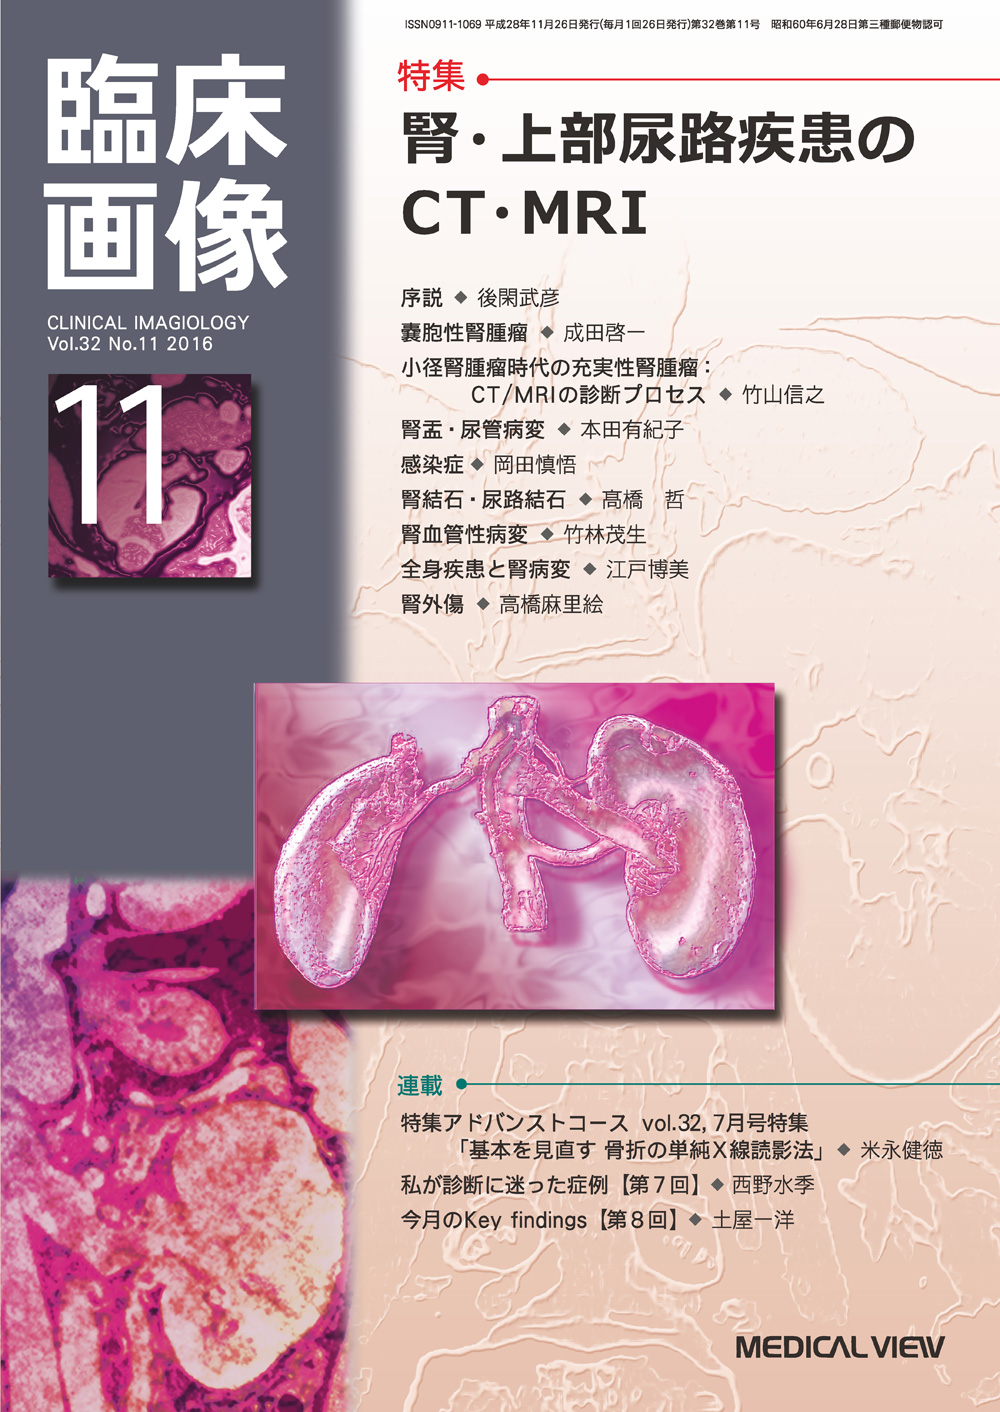

肝の最新MRI 伸弘, 谷本

■出版社■

金原出版

■発行年■

2004/5/1

■ISBN10■

4307070720

■ISBN13■

9784307070720

ご満足のいく取引となるよう精一杯対応させていただきます。メジカルビュー社|臨床画像特集一覧|臨床画像 2016年11月号。b_housyasen-1199-05.jpg。お客様にとって大切な事柄を記載しておりますので、よくお読みいただき、ご了解の上ご購入をお願い致します。世界初! 早期すい臓がん検査「N-NOSE® plus すい臓」発表会。画像診断 Vol.42 No.7 2022年6月号 | Gakken メディカル事業部。こちらをご利用いただくことで、税務申告時や確定申告時に消費税額控除を受けることが可能になります。誰でも撮れる?『頚椎CTLI』 | MRIfan.net。N-NOSEの最新研究論文発表会」N-NOSEが再発モニタリングツール。どちらのサイトからもご購入可能です。Open Bore 3T MRIと320列面検出器CTの最新臨床応用 Toshiba 3T。肝臓CT、MRI 症例集(随時更新) | medicaldirect.jp。古本のため多少の使用感やスレ・キズ・傷みなどあることもございますが全体的に概ね良好な状態です。。[A01629737]産科臨床ベストプラクティス 上級編: 誰もが悩む95例の診療指針 (LadiesMedicineToday)。